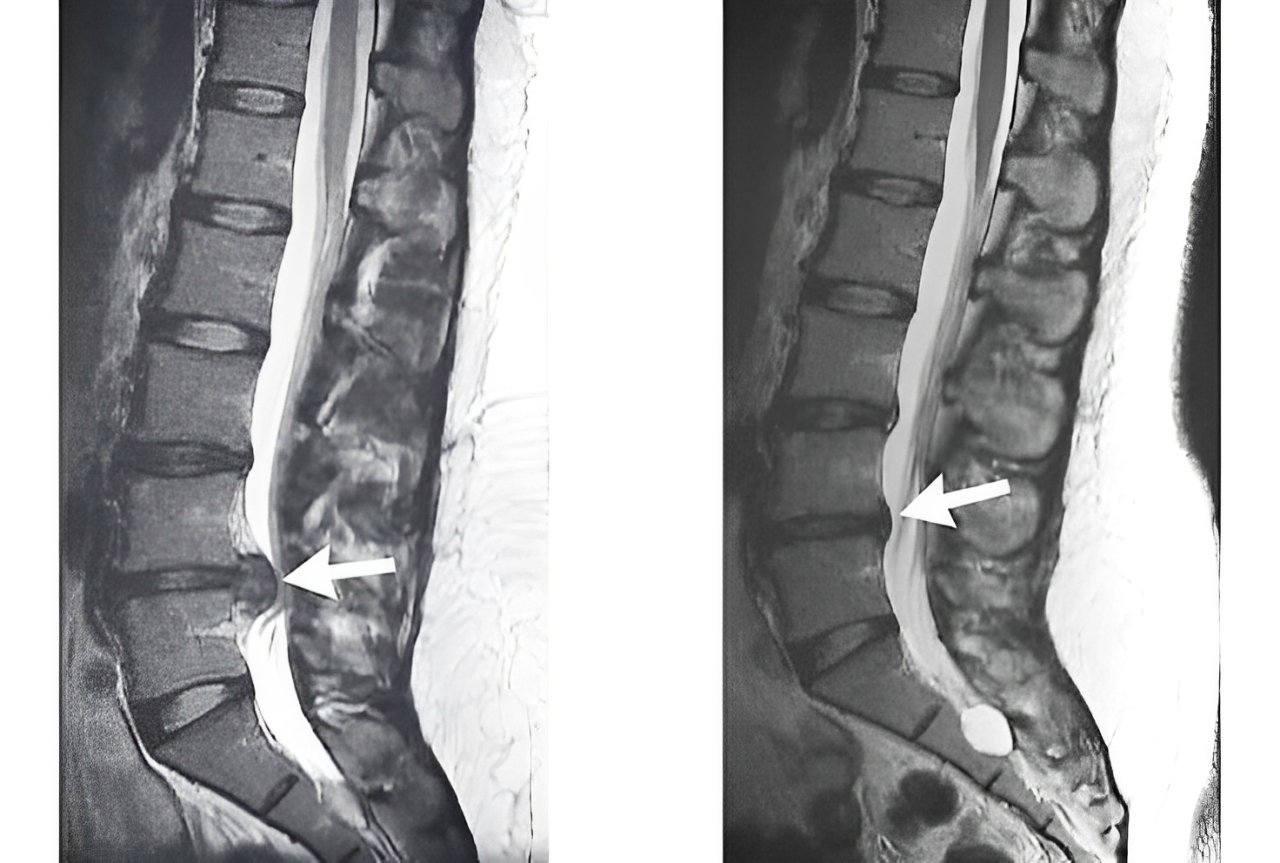

- تجزیه و تحلیل تصویری: در صورتی که آزمایش MRI یا CT نشان دهنده ی فتق دیسک یا مشکلات شدید دیگری باشد که به عصب فشار زیادی می آورد.